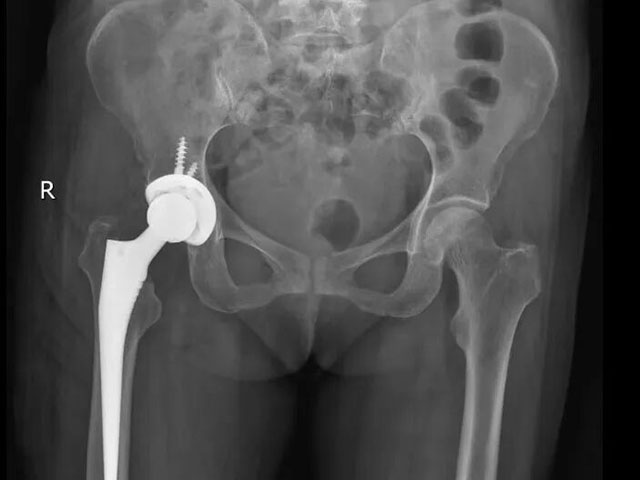

入科后,敖亮医生对王阿姨的病情进行全面研判:结合其年龄、骨折类型及身体基础状况,最终确定采用左全髋关节置换术。

“全髋关节置换术能直接替换受损的髋关节结构,术后患者疼痛缓解明显,可更快恢复行走功能,大幅缩短康复周期,尤其适合骨折移位明显、年龄较大的患者。”敖亮医生向王阿姨及家属详细说明手术方案及优势,获得了家属的认可。

手术过程中,敖亮医生精准操作,顺利为患者植入人工髋关节假体,确保假体位置与角度适宜,保障术后髋关节功能恢复。

术前

术后患者影像资料